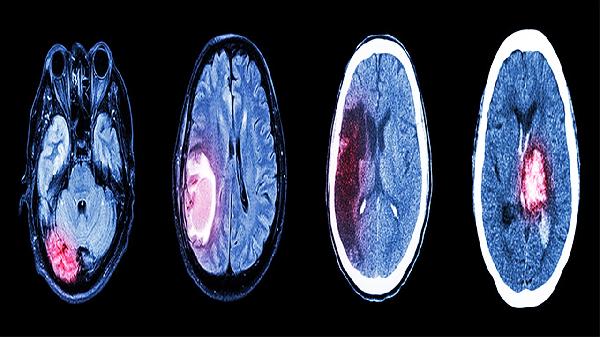

垂體上方與視交叉相鄰,腫瘤向上生長可壓迫視神經(jīng)通路,導致雙顳側(cè)偏盲或視力下降。早期可能僅表現(xiàn)為閱讀困難、視野缺損,眼底檢查可見視乳頭水腫。磁共振成像能明確腫瘤與視神經(jīng)的關(guān)系。對于壓迫性病變,經(jīng)鼻內(nèi)鏡垂體瘤切除術(shù)可解除壓迫,術(shù)后視力恢復程度與受壓時間長短相關(guān)。